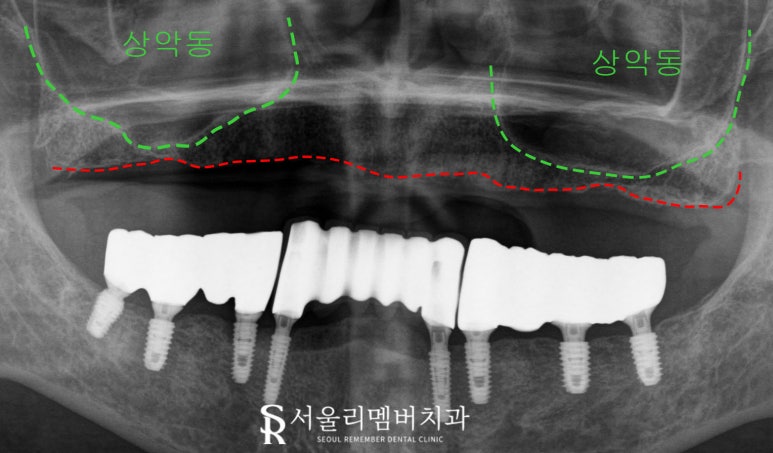

panorama x-ray

정밀하게 보기 위해

신림역 치과 에서

파노라마 촬영을 합니다.

밑에 있는 크라운과 잘 맞물리기 위해

픽스처 식립을 좌측 5개, 우측 5개 심기로 하고

앞니는 양쪽 픽스처의 도움을 받아

크라운을 브릿지 형태로 연결해서 쓰기로 합니다.

위치를 어떻게 해야 알맞게 식립 할 수 있을지

자세히 보다가

위쪽 잇몸뼈가 얇아져 있는 걸 알 수 있습니다.

우리 얼굴뼈 안에는

얼굴의 무게를 줄이며

코를 통해 들어온 노폐물을

걸어주는 역할을 하는 빈 공간이 있는데

이것을 상악동이라 부릅니다.

이 빈 공간 바로 아래 위치해 있는 어금니 부위에 implant를 해야 되는데 사진을 보니

뼈가 부족해

이것을 거상하는 시술을 같이 병행하는 것이

좋겠습니다.

이 시술은 고난도 수술로 꼽히며

점막이 얇고 찢어지기 쉬워

기술력이 중요시됩니다.